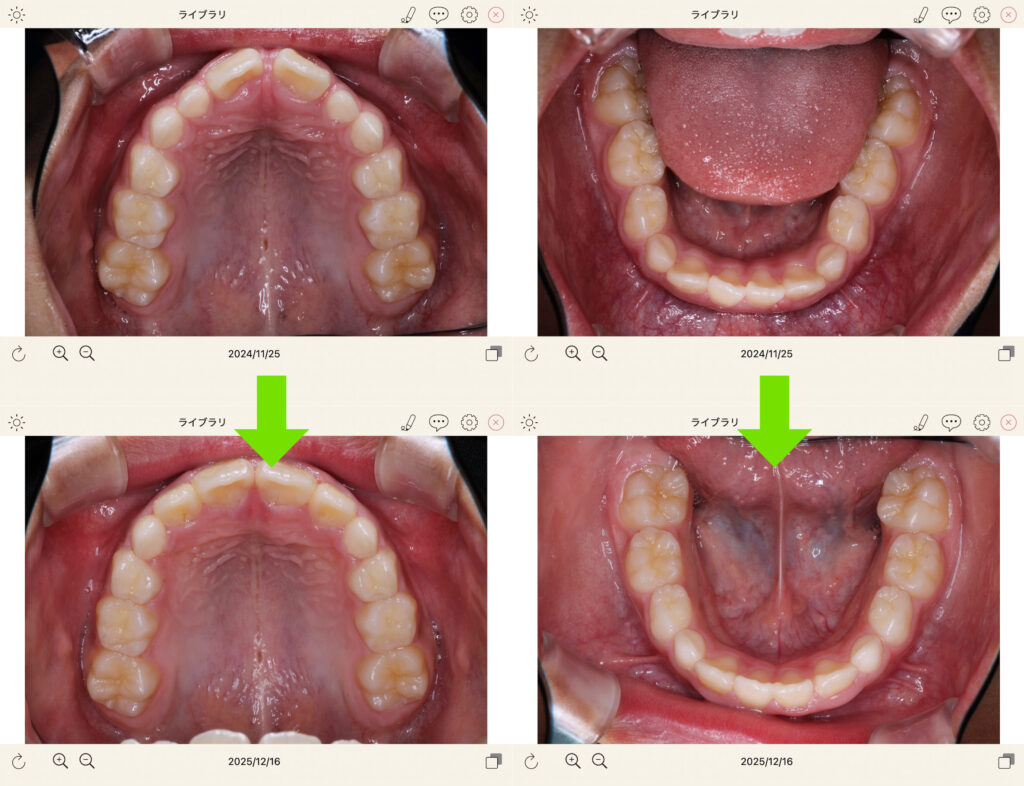

別件で小児矯正。新規開業から1年経ち、以前の中村歯科からのお子様もたくさん来院し、親戚のおじさんのように子供たちの成長が嬉しい限りです。

治療中のお子様も日々改善する歯並びに楽しく来院してくれています。

地元青葉台でもお子様のご紹介をたくさんいただきありがたく思っております。

健全な顎の成長を伴う小児矯正が当院の強みです!

歯並びだけでなくお顔の健全な成長やお口周りの機能の改善(飲み込み、口呼吸、お口ポカン)させます。

是非ご相談いただければと思います!